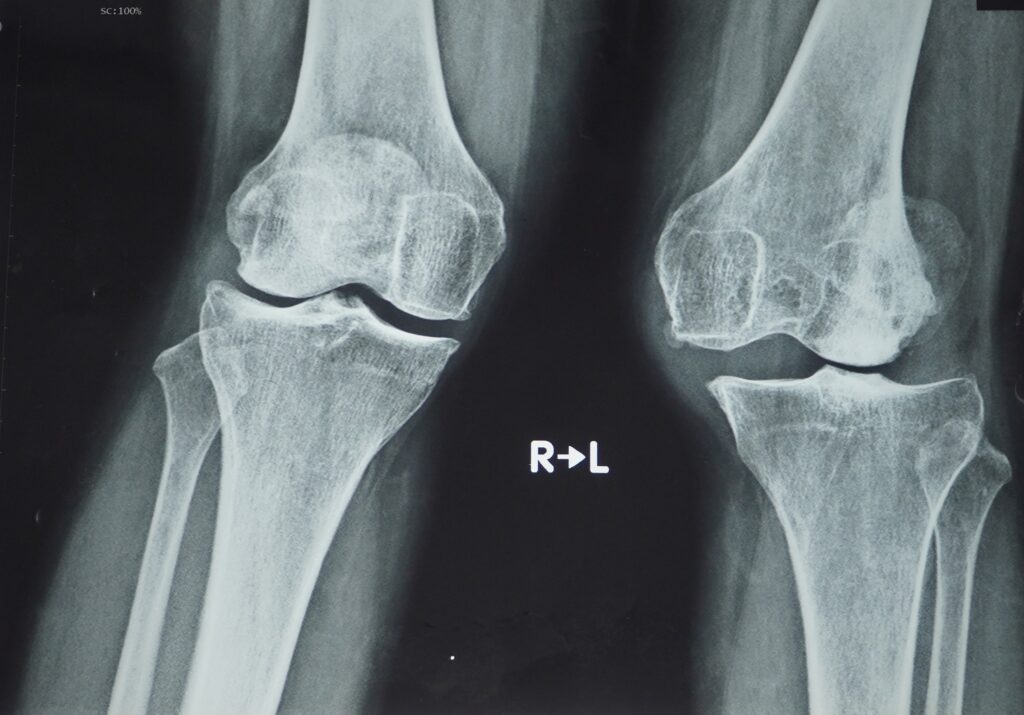

Khi chụp X-quang có thể thấy sụn giữa các xương có dấu hiệu bị tổn thương, gây sưng, đau hoặc cứng. Không gian giữa các khớp gối bắt đầu thu hẹp lại, khiến người bệnh cảm thấy khó khăn khi đi bộ, chạy, cúi, quỳ… Triệu chứng cứng khớp ở giai đoạn 2 cũng diễn ra ở giai đoạn 3 nhưng với tần suất thường xuyên hơn, nhất là sau khi ngồi một thời gian hoặc thức dậy vào buổi sáng.

- Dựa trên triệu chứng và tình trạng bác sĩ sẽ chỉ định thực hiện một số xét nghiệm như chụp X-quang, chụp cắt lớp vi tính (CT), chụp cộng hưởng từ (MRI)…